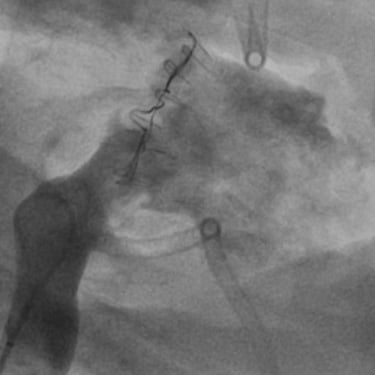

The tech has been developed through 3 years of testing and iterations based on test data and user input including bench at Resolution Medical, beating heart model at Lifetec Group and successful In-vivo deployment in an animal modal at the pre-clinical reference lab at IMMR/Veranex in Paris with extremely encouraging results.